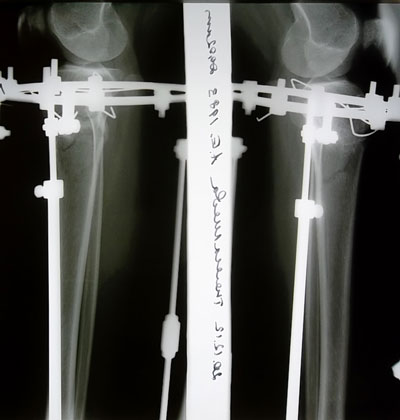

- Диагноз: О-образная деформация ног

- Какую операцию Вы планируете сделать.: по исправлению кривизны ног

- Дата операции.: 05.04.2012